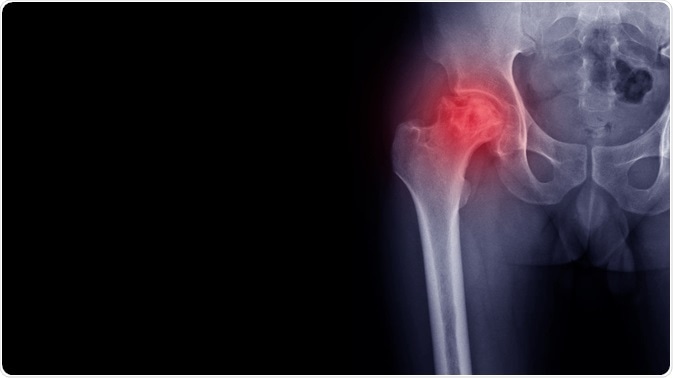

Osteoarthritis (OA) is a major cause of pain and disability in daily life, and a heavy healthcare expense as well. Both of these can cause significant distress and psychosocial impact.

Most people with OA feel their joints are undergoing progressive breakdown without recovery, and that joint replacement is the only way out. This is largely because of discussions with medical professionals where the words “wear and tear” are used. Thus, they feel they cannot do anything to help improve joint function. This acceptance of a flawed model of biomechanical degradation of joint structure prevented their even recognizing that they experienced periods of improvement with few symptoms, and other periods of flare-ups, which could not be explained by this model. This may account for the often-perceived need to rest, pace activity and protect the joints and the poor adherence to exercise- and lifestyle-mediated improvements that actually reduce joint pain and improve joint function. Moreover, pain does not occur in direct relation to the joint damage or the activity undertaken. Such wrong concepts should be addressed during health consultations.